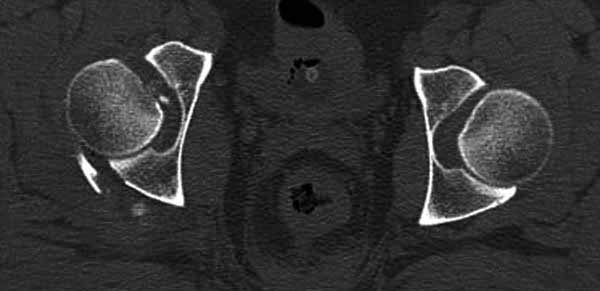

Имя     : 3 Fem head  CT.jpg

Тип     : image/jpg

Размер  : 27916 байтов

Описание: отсутствует

Url     : http://weborto.net:8080/pipermail/ortho/attachments/20111231/d311d17a/attachment-0017.jpg